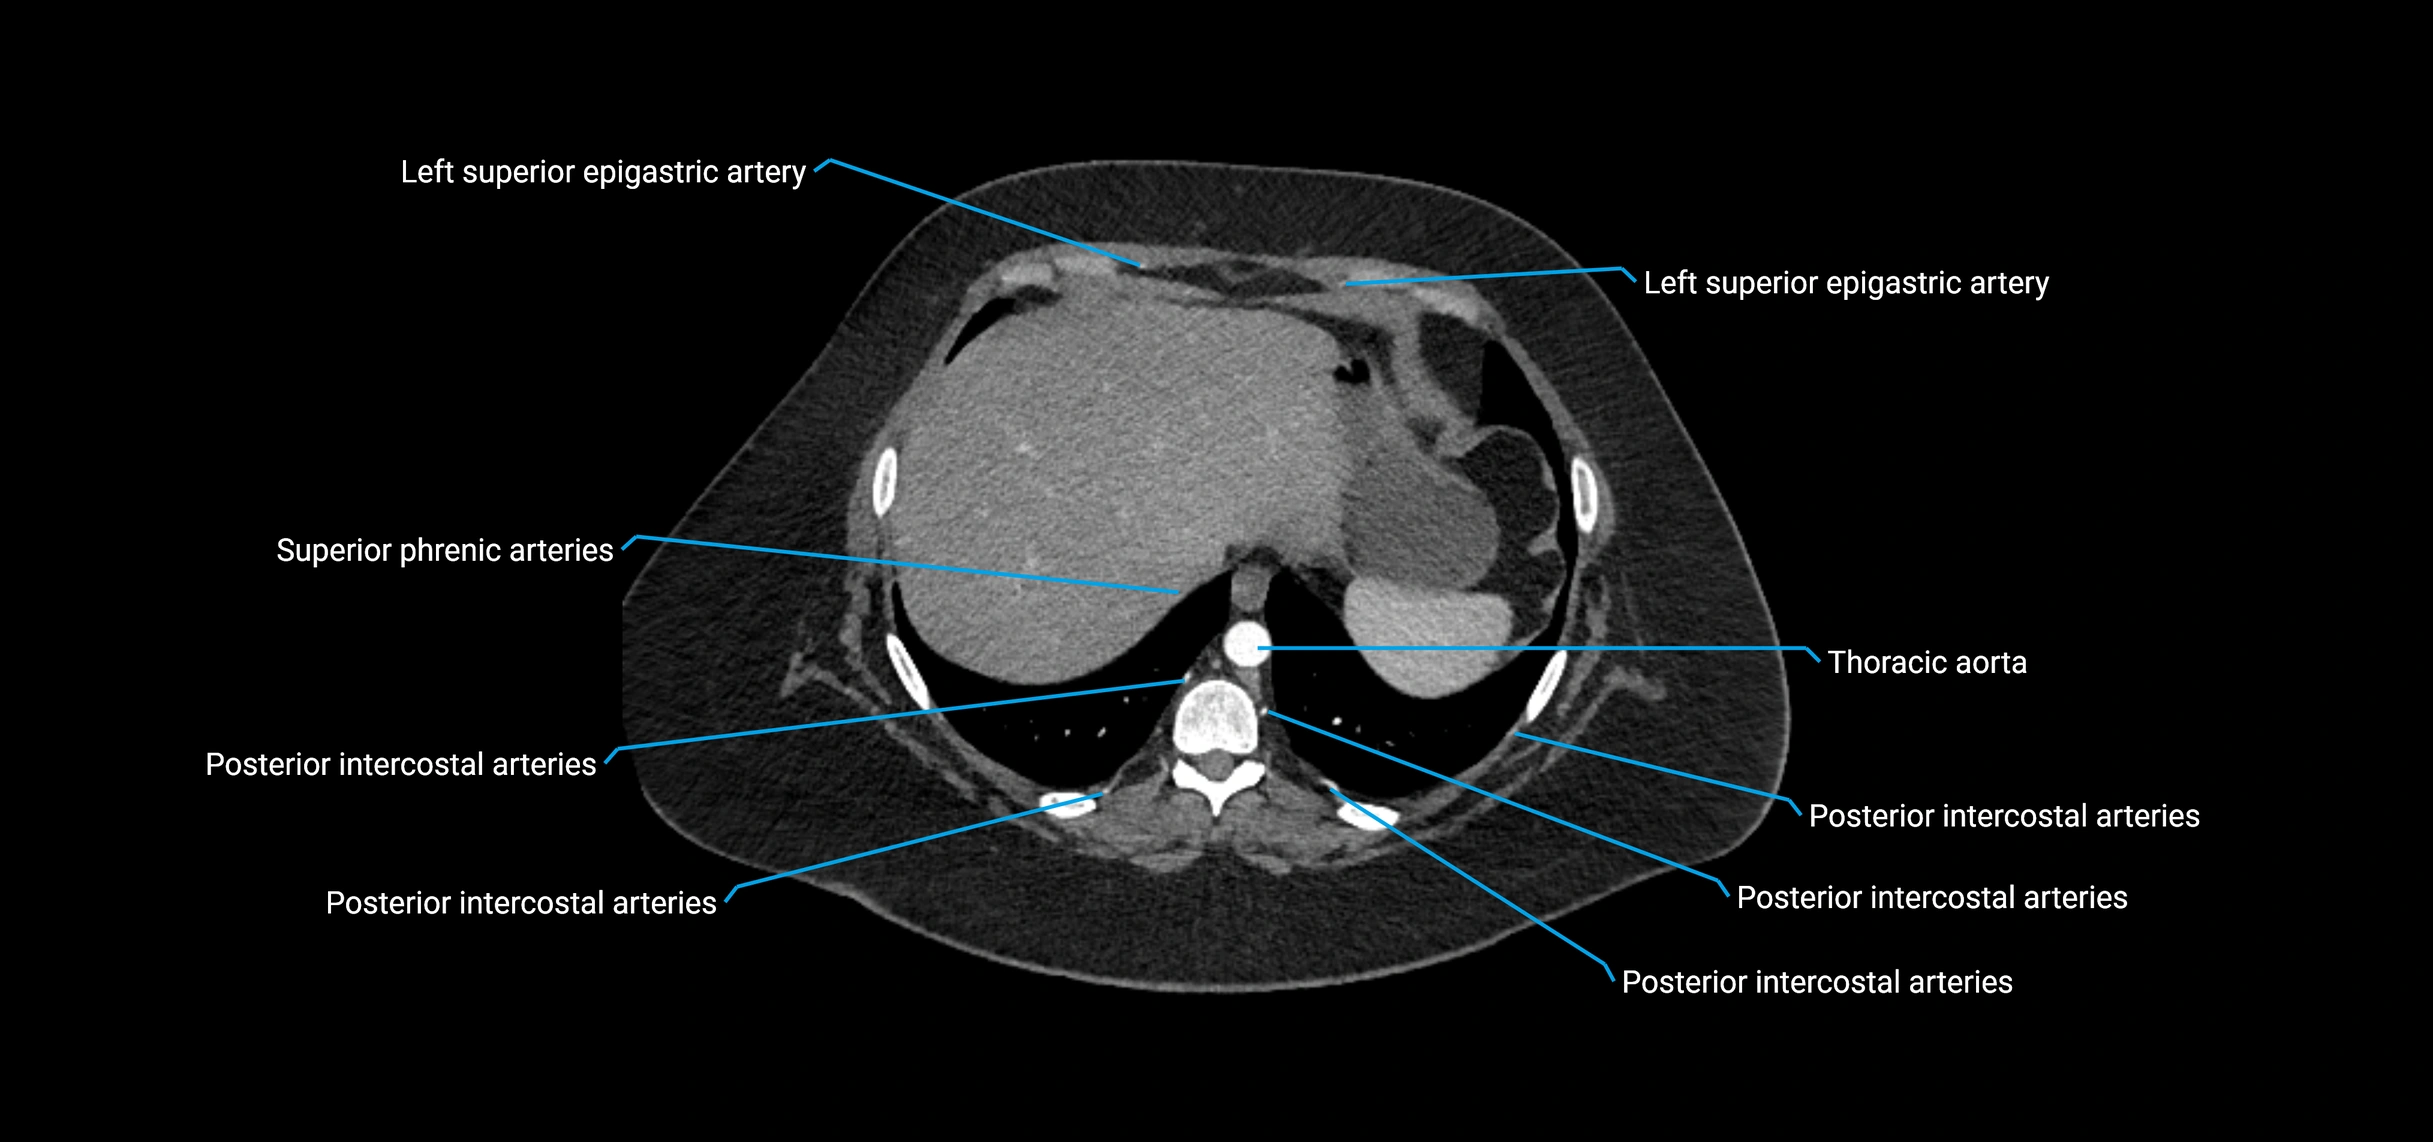

CT images

image

CT Appearance

Non-contrast CT:

• Appears as a tubular soft tissue structure anterior to vertebral bodies

• Calcified atherosclerotic plaques appear as hyperdense foci along the wall

• Useful for screening abdominal aortic aneurysm (AAA) size and mural calcification

Contrast-enhanced CT (CTA):

• Gold standard for abdominal aortic imaging

• Provides excellent detail of lumen, wall, aneurysm, thrombus, and branch vessels

• Multiplanar and 3D reconstructions help in aneurysm measurement, stent graft planning, and dissection evaluation

• Detects acute rupture, traumatic injury, or occlusion with high sensitivity